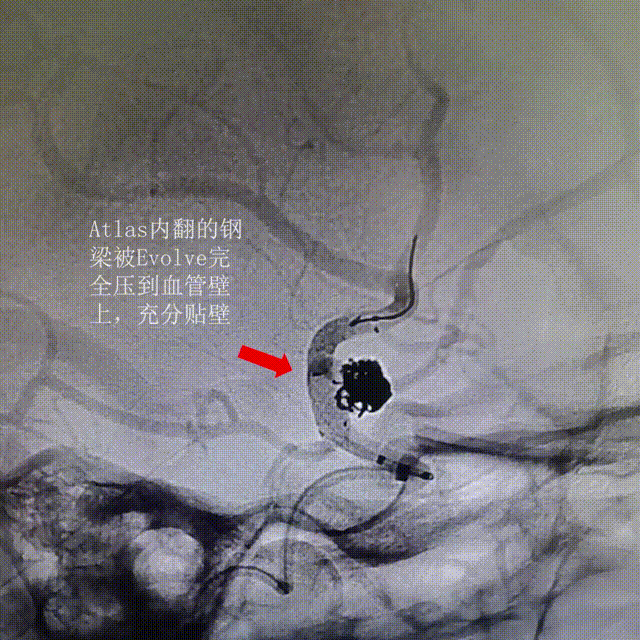

讨论后相信Evolve的支撑力,尝试先释放一部分FD后推挤系统增张,让Evolve充分鼓起贴壁,将内翻的钢梁压到血管壁上,如Evolve推不开则回收。

顶住Evolve支架钢丝,退XT-27支架导管,支架远端定位在Atlas的远端Mark以近2mm,并顺利打开。

由于血管平直,继续顶住Evolve支架钢丝,退XT-27支架导管,当支架释放至颈内C7段时,整体推支架系统增张,让瘤颈口处的支架充分贴壁,将内翻的钢梁压到血管壁上。

术后3D造影:支架打开充分,全程贴壁,各分支血管血流通畅,可看到内翻的Mark点也被Evolve贴到了血管壁上,充分体现了Evolve足够强的径向力,预示着Evolve对动脉瘤合并狭窄应用或许是一个不错的选择。